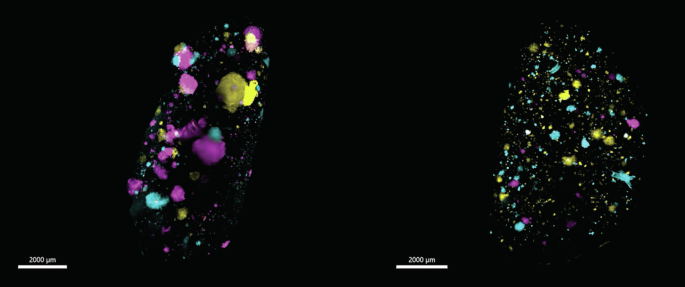

Lung lobes acquired via light sheet microscope from IV-injected mouse (left) and MFP-injected mouse (right). SVT BPs (Cyan, Yellow Green, Magenta, Purple, Orange, White) and blood vessels (grey) are shown. Scale bar 2000 μm.

We next compared the heterogeneity of lung metastasis after: orthotopic transplantation of cancer cells into the inguinal mammary fat pad (MFP) of 4 mice, where intravasation relies on active shedding from the primary tumour into the vasculature, followed by extravasation into the lungs; and intravenous tail vein injection (IV) of cancer cells into 5 mice, where the intravasation process is bypassed. Here, 100,000 combinatorial SVT cells from the same cell line were injected into multiple mice to enable the differences in colour distributions and frequencies to be compared across animals and assays.

We then took advantage of the optical barcoding technology to study intra-metastatic heterogeneity in both groups. We showed that regardless of the mode of injection, there were significantly fewer polychromatic metastases than monochromatic metastases in the mouse lung tissue (Fig. 3u). Despite being less abundant, the polychromatic metastases showed a trend of being larger in volume compared to the monochromatic metastases in the lungs of both IV and MFP-injected mice (Fig. 3v). These findings conform with earlier studies undertaken in a transgenic MMTV–PyMT mouse model12 and a human cell line MDA-MD-231 and PDX MFP-injected mouse model11.